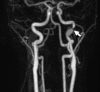

Carotid artery dissection is an important cause of stroke in young adults. When focal neurological deficit or classic traumatic history is absent, the diagnosis can be challenging. This lesson reports an interesting case of a patient in whom pupillary dysfunction was the presenting sign of acute dissection of carotid artery.